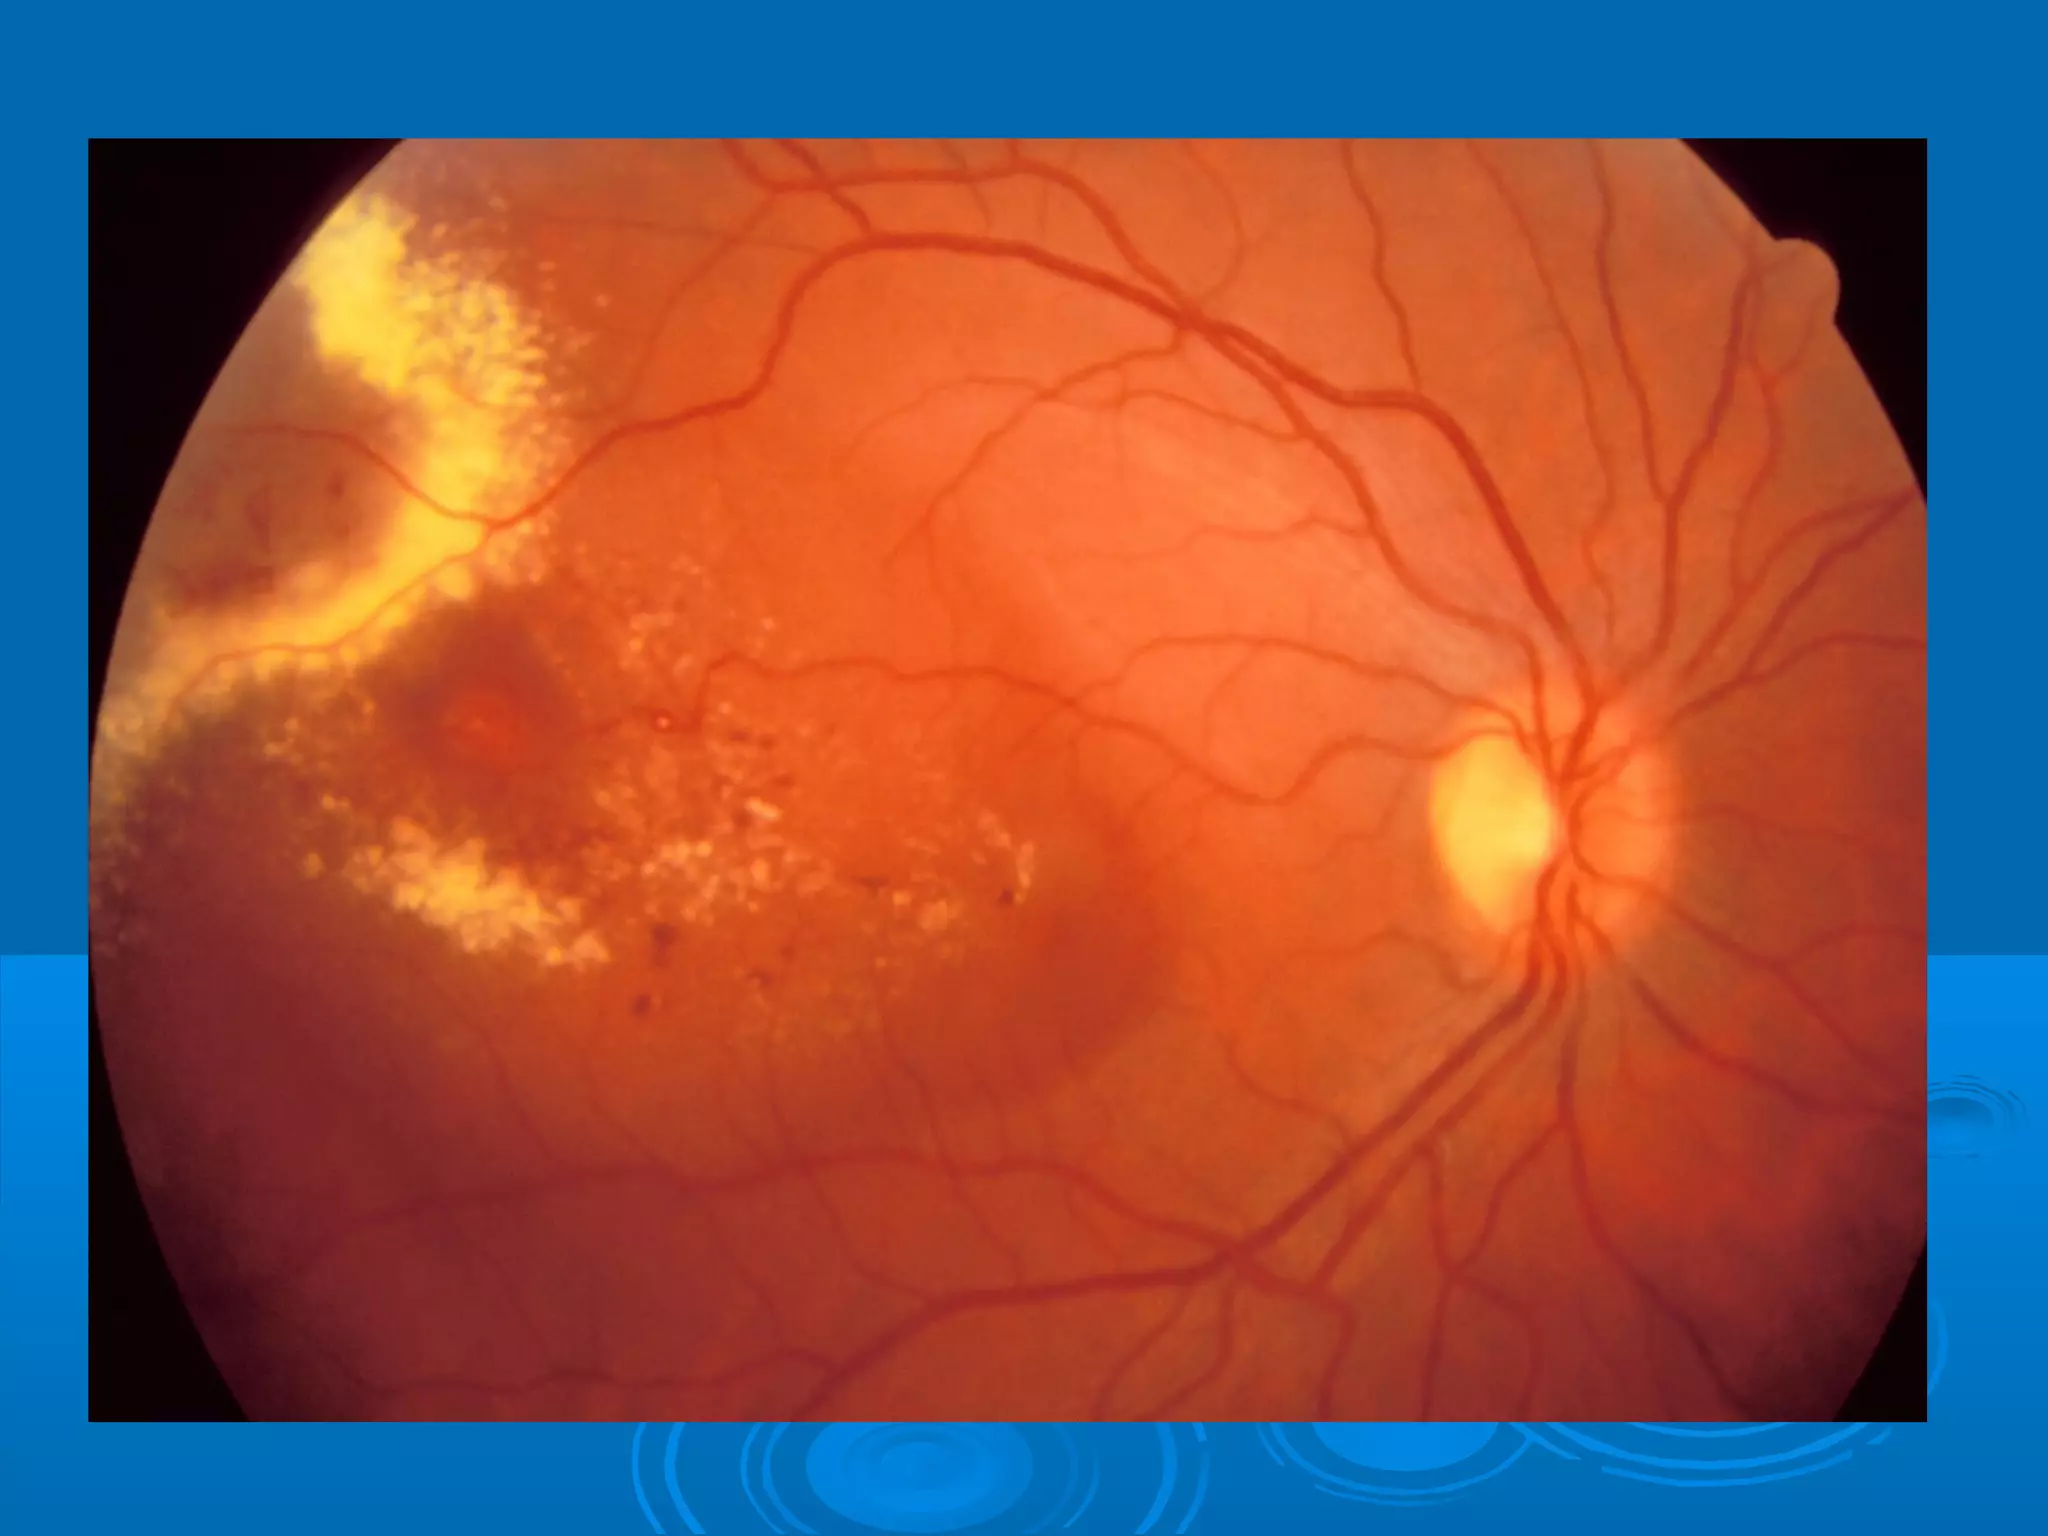

Болезнь Коатса - это идеопатическое заболевание, характеризующееся полиморфными изменениями сосудов сетчатки с массивной экссудацией, чаще всего у детей и подростков, с преобладанием среди мальчиков. Эпидемиология показывает, что заболевание проявляется, как правило, в возрасте 8-16 лет, но возможно его обнаружение и у взрослых. Основные проявления включают ретинальные аномалии, субретинальную экссудацию и постепенно прогрессирующую потерю зрения.